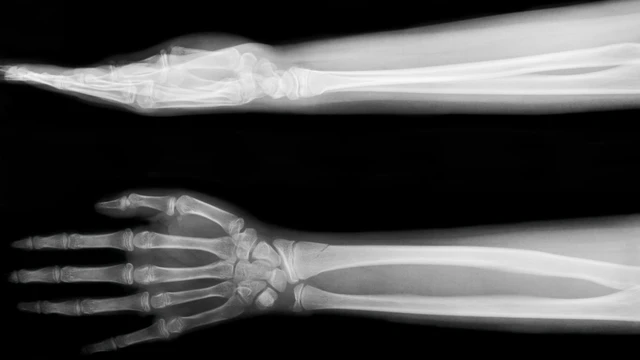

X-quang bàn tay là kỹ thuật chẩn đoán hình ảnh phổ biến giúp phát hiện các bất thường về xương khớp, chấn thương hay dị vật. Bài viết này sẽ cung cấp chi tiết về các trường hợp cần chỉ định và cách đọc kết quả chẩn đoán chuẩn xác nhất.